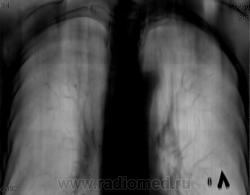

По томограммам не понятно что хотели получить? Интересовали эти маленькие плотные очаги?

Справа на верхушке инфильтративная тень. Слева в задних отделах мелкие буллы.

На последнем срезе тень в 1 сегменте, мелкие полости в верхних долях с обеих сторон.